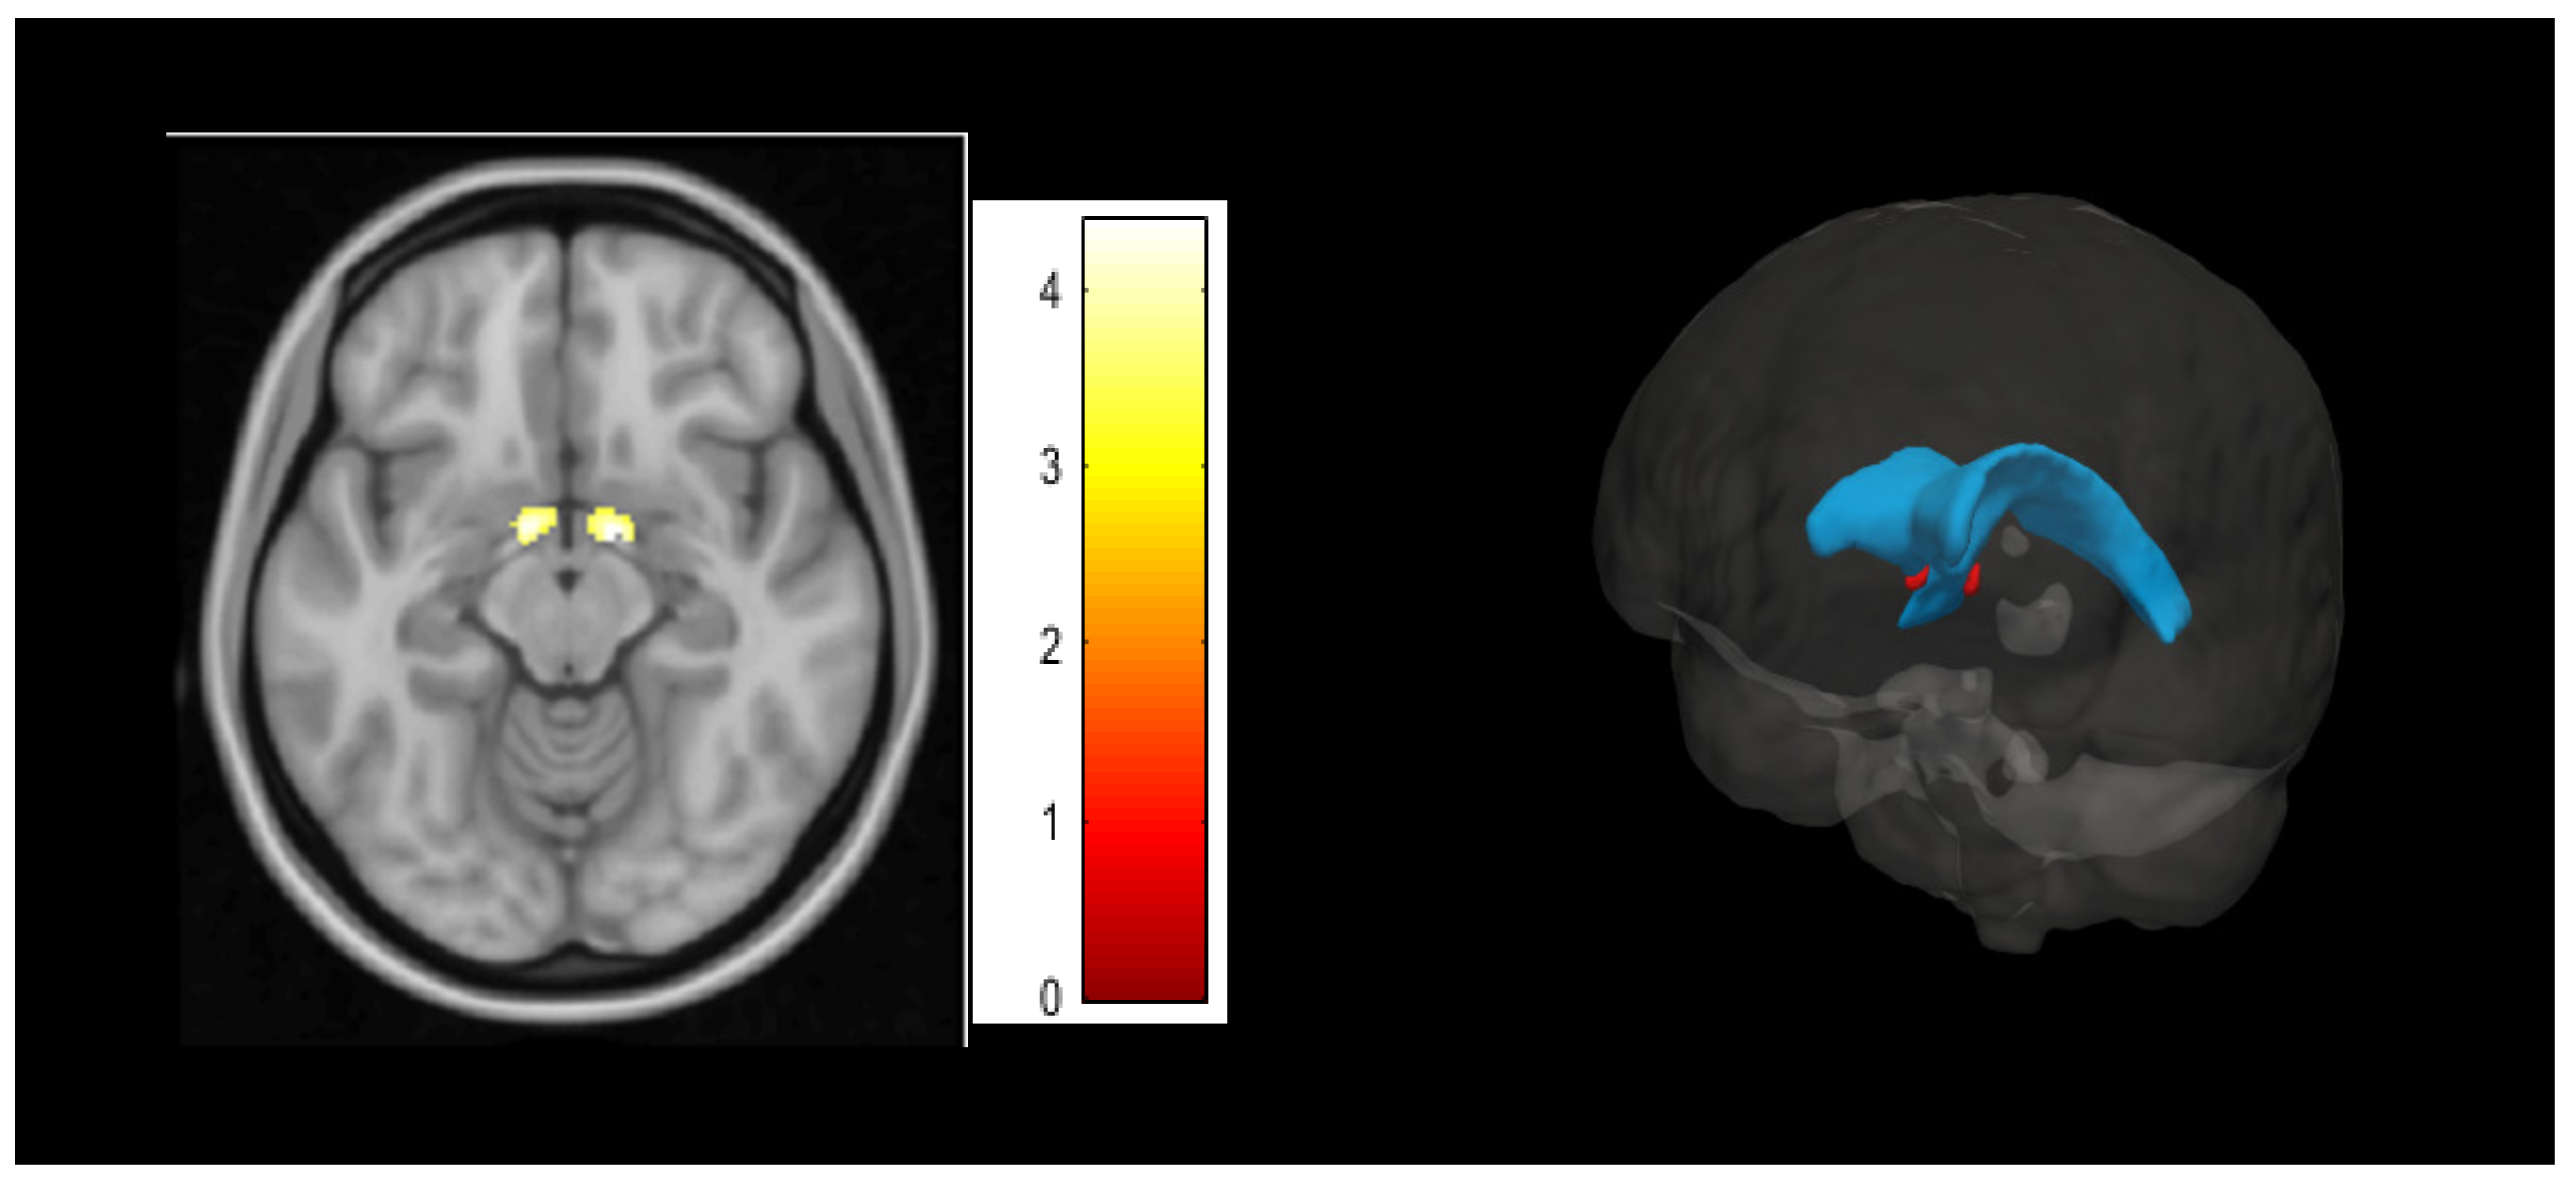

3.2. Psychological Inflexibility Clusters in Voxel-Based Morphometry Analyses

- Theiss, J.D.; Ridgewell, C.; McHugo, M.; Heckers, S.; Blackford, J.U. Manual segmentation of the human bed nucleus of the stria terminalis using 3 T MRI. Neuroimage 2017, 146, 288–292. [Google Scholar] [CrossRef]

- Motzkin, J.C.; Philippi, C.L.; Oler, J.A.; Kalin, N.H.; Baskaya, M.K.; Koenigs, M. Ventromedial prefrontal cortex damage alters resting blood flow to the bed nucleus of stria terminalis. Cortex 2015, 64, 281–288. [Google Scholar] [CrossRef] [PubMed]